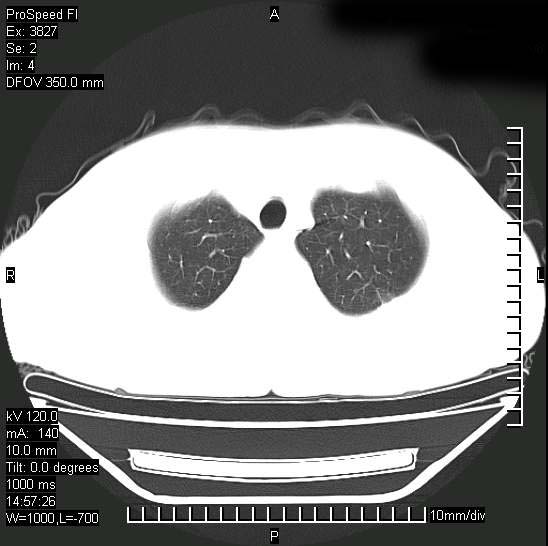

男性,一月前出现右侧肋区疼痛,较剧烈,干咳,无发热,自诉使用抗炎药后缓解,几天前又出现左侧剧烈疼痛,

发热,体温38。9,今天ct,考虑左侧包裹性脓胸,胸腔积液,右上中肺小斑片影,结核/炎症?胸水未见恶性细胞。